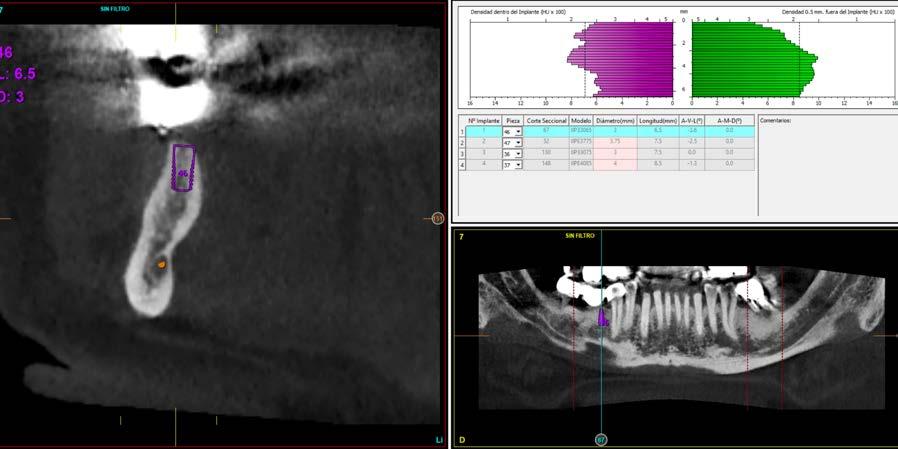

Explantación atraumática y recambio de implantes mal posicionados y afectados por periimplantitis sumado a la utilización de implantes estrechos y cortos. Enfoque mínimamente invasivo de un caso de atrofia ósea moderada

42 | INVESTIGACIÓN CLÍNICA